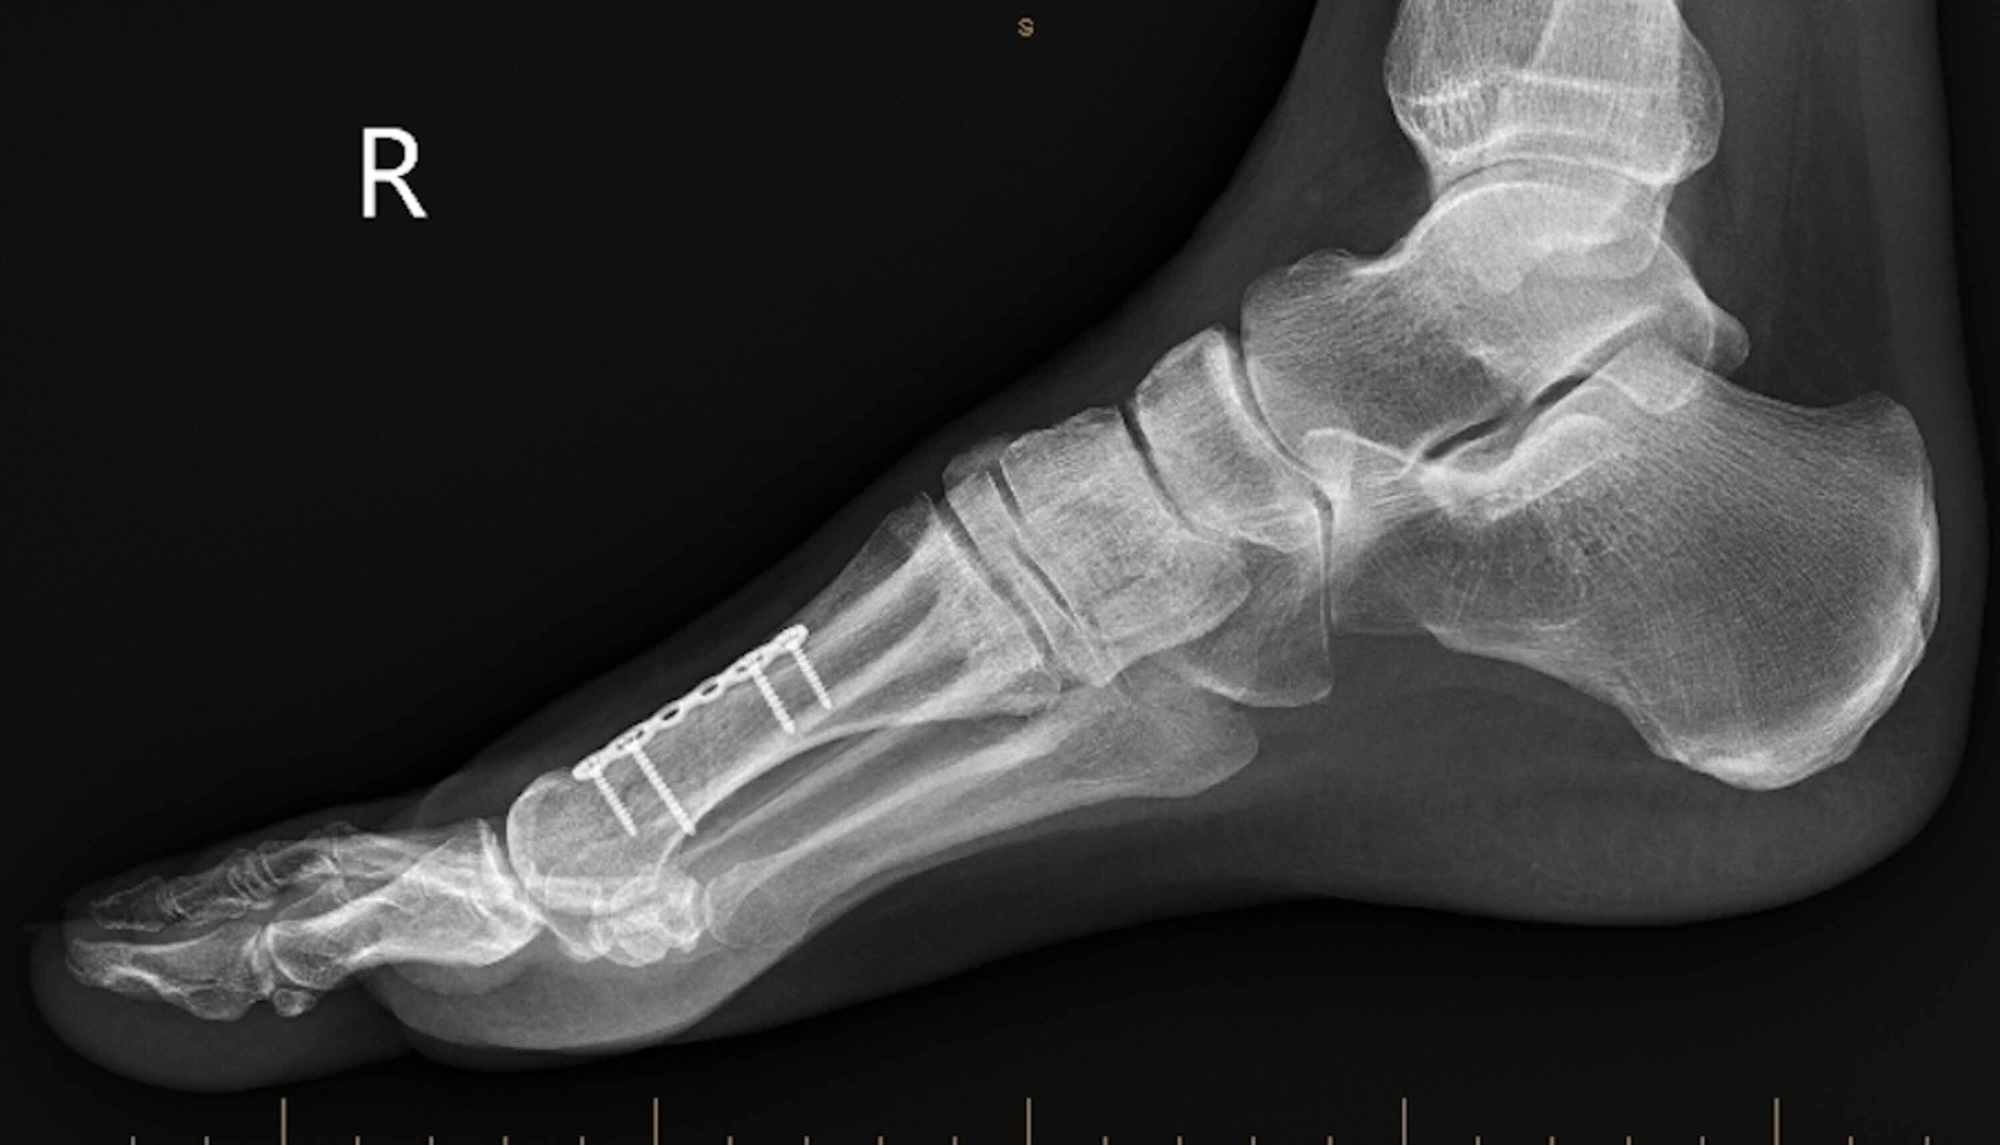

Surgical Realignment of a Dorsiflexed Metatarsal Fracture Cureus Boot Fracture Metatarsal This is normal for 3 to 6 months after your injury. You may walk on the. It can take up to 6 to 12 weeks for this fracture to heal. A metatarsal fracture occurs when one of the long bones of the midfoot is cracked or broken. This may be due to sudden injury (an. Most metatarsal fractures are managed. Boot Fracture Metatarsal.

First metatarsal fracture Image Boot Fracture Metatarsal Your foot may be swollen and painful. If required, you will also be provided with crutches. Swelling is often worse at the end of the day. Diagnosis is made with plain radiographs. You will be provided with a removable boot support for the foot. A metatarsal fracture occurs when one of the long bones of the midfoot is cracked or. Boot Fracture Metatarsal.